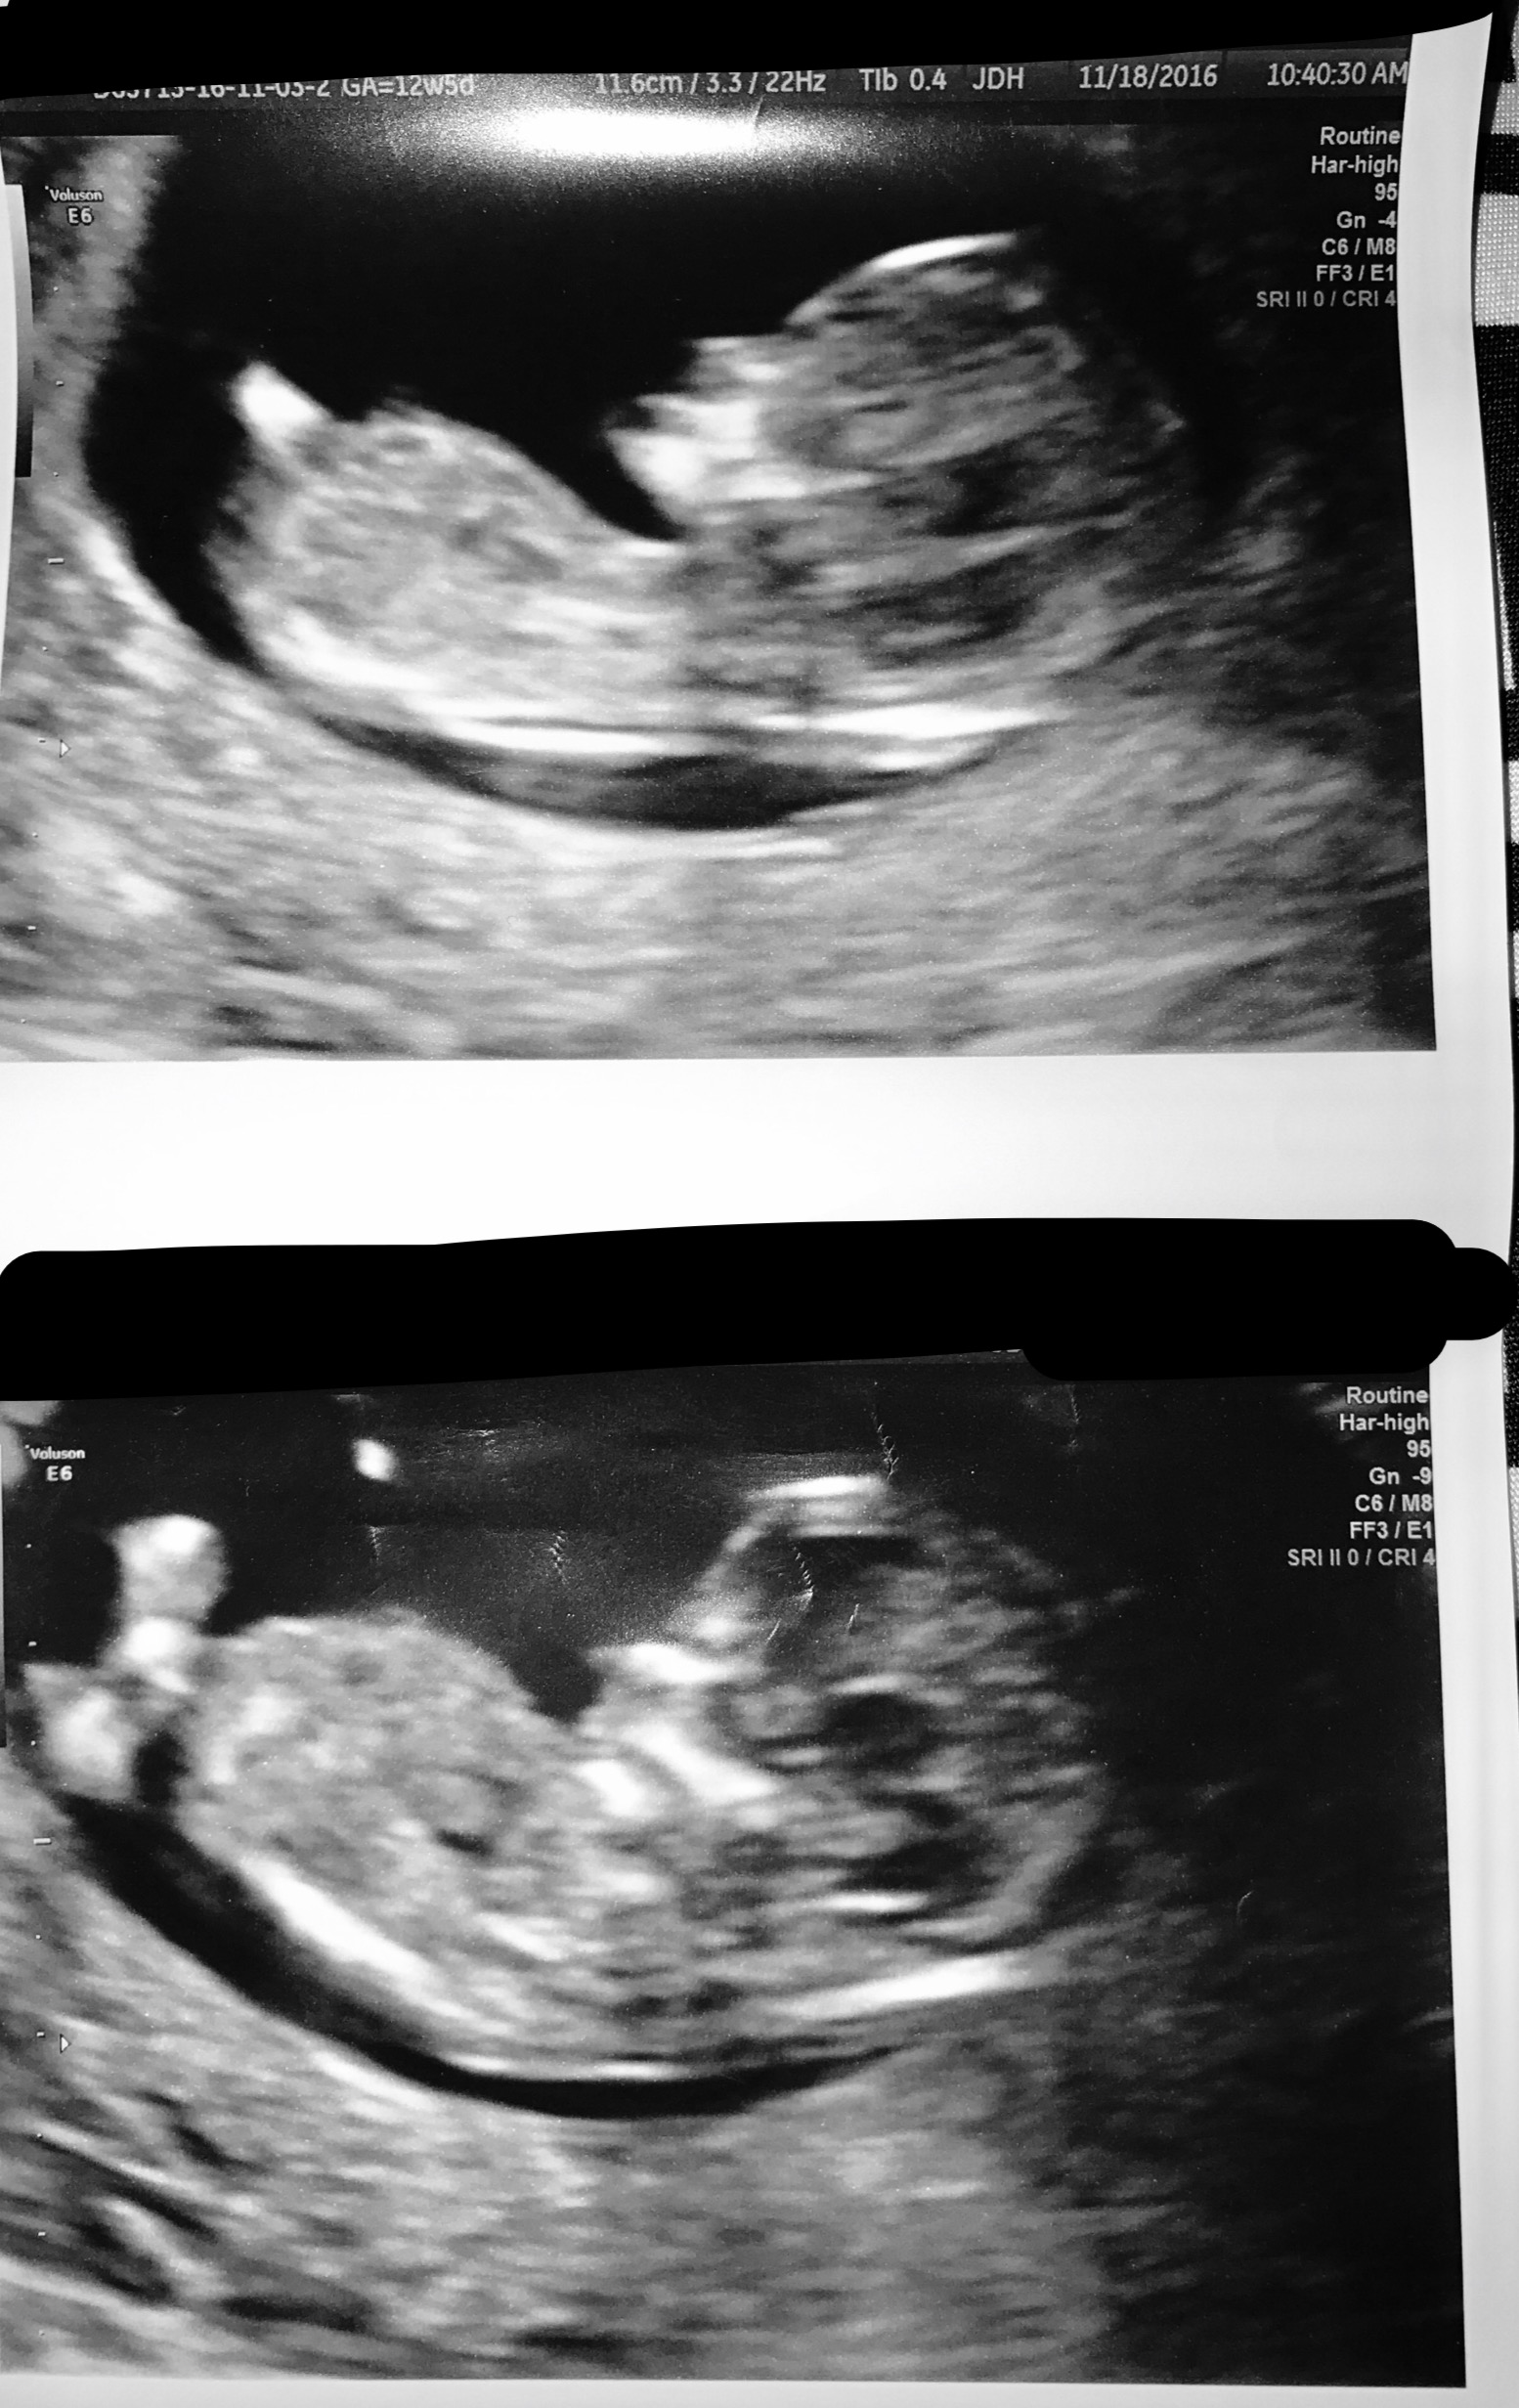

I think Boy, Husband thinks girl. Any guesses?Attachment 33883

Boy

From the top pic I lean Boy

I'm thinking boy too.